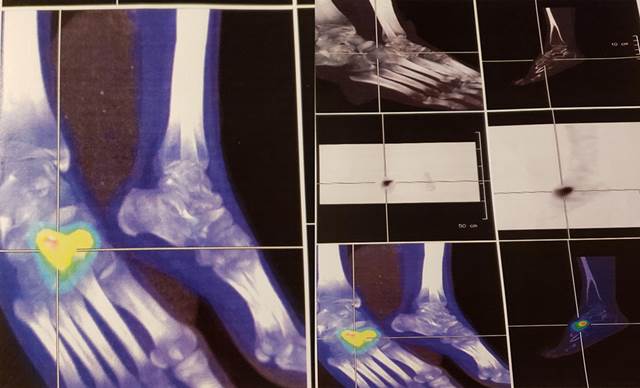

A los tres días se constató aumento de los signos inflamatorios del tobillo derecho. Se realiza centellograma óseo que evidenció lesiones óseas activas hiperémicas en tarso derecho, primer y segundo cuneiforme, compatibles con planteo de osteomielitis (Figura 1).

Figura 1: Centellograma óseo. Se observa hipercaptación a nivel del tarso derecho.